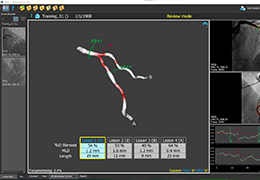

ANYTHINK 经导管主动脉瓣膜置换术分析系统